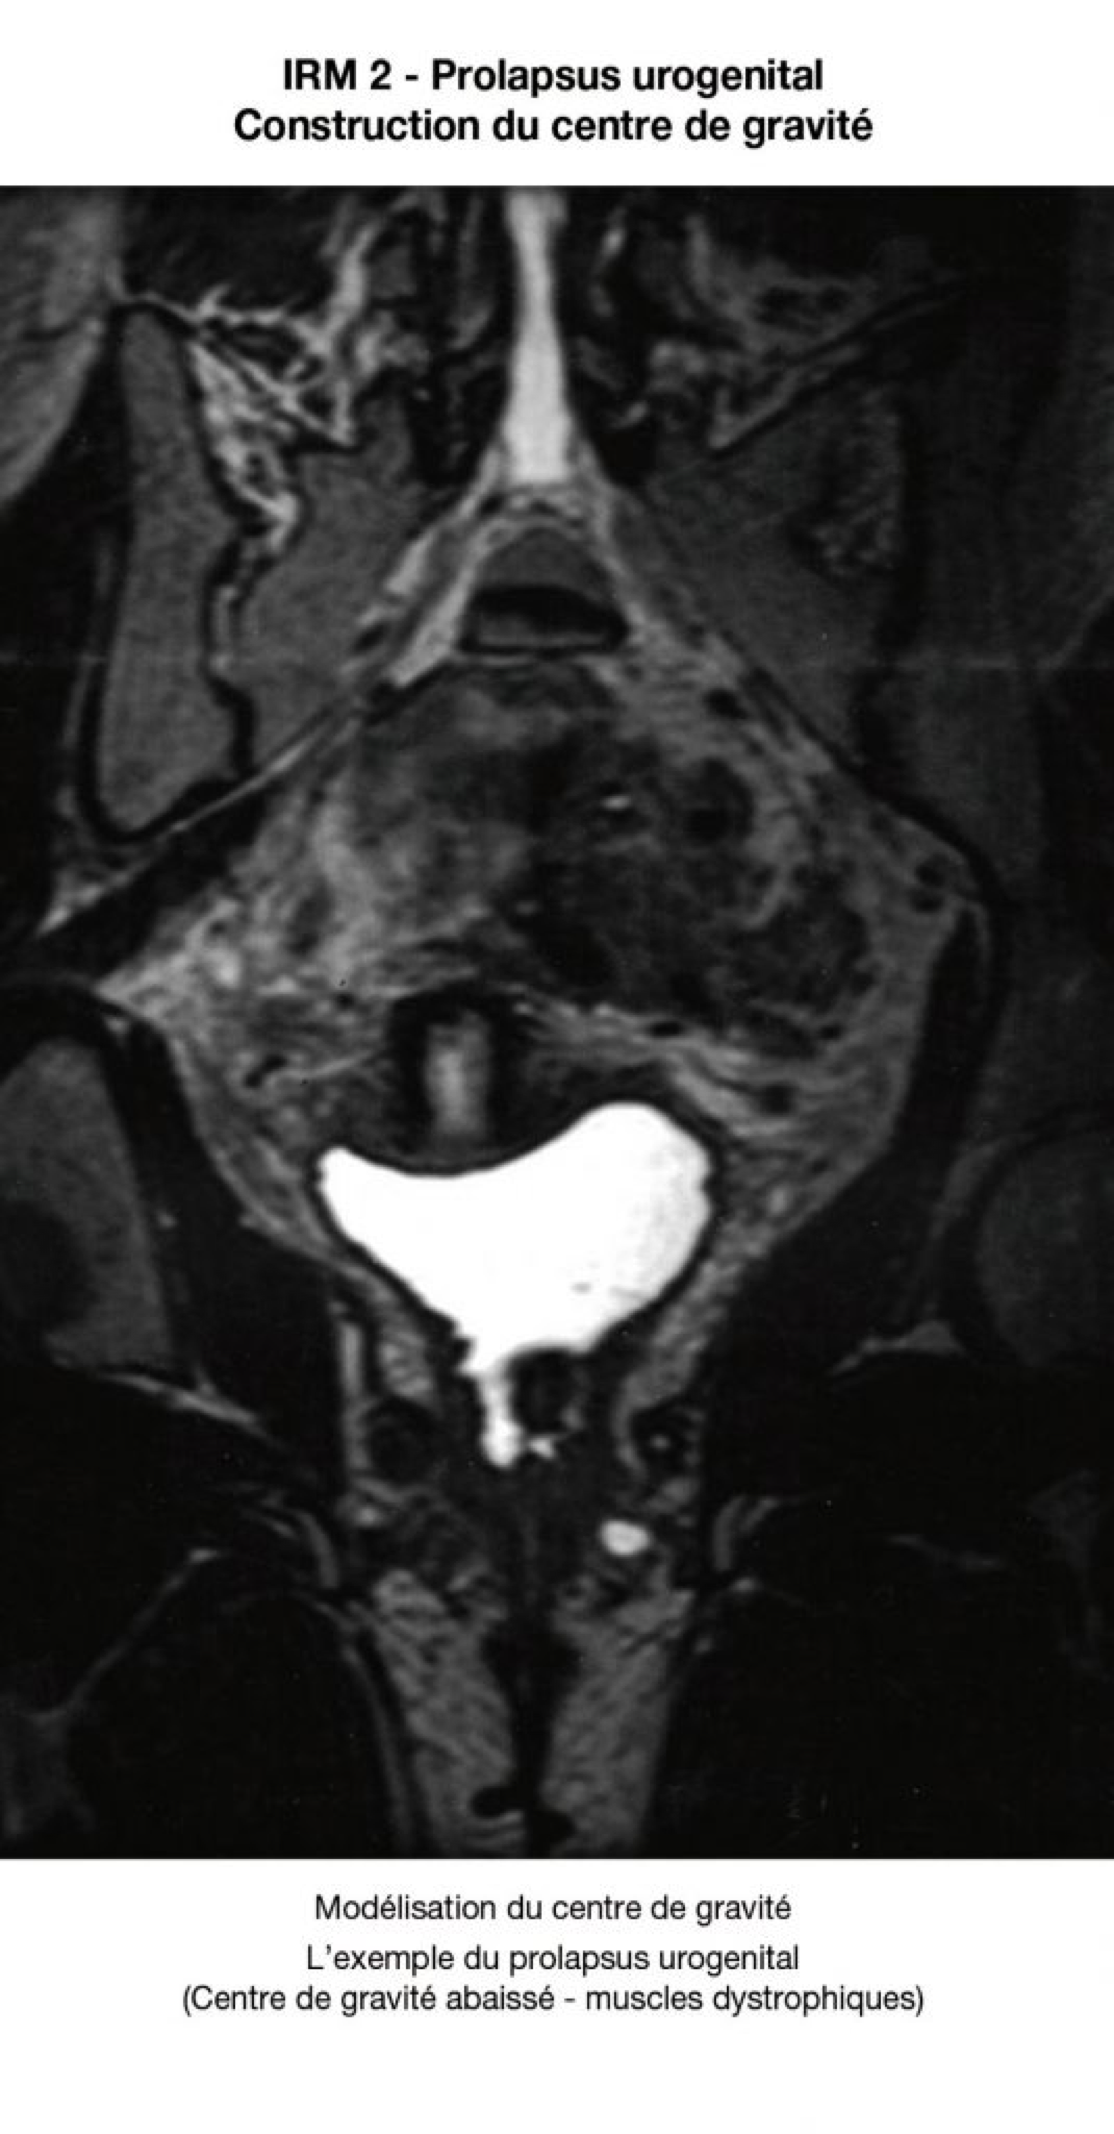

La forme des repères osseux est immuable. Les limites des parties molles, elles, sont variables. Les parties molles ne se limitent pas au plancher pelvien, elles incluent les obturateurs internes .La variation de volume des obturateurs va faire varier la position du centre de gravité du paraboloïde.

Le « vecteur résultant » des forces gravitationnelles et abdominales va être renvoyé plus ou moins haut, plus ou moins bas, selon que ces muscles seront épais (femme jeune - centre de gravité élevé), ou seront atrophiques ou délabrés (centre de gravité abaissé).

9. Périnée prolapsus

LE VECTEUR DE LA PRESSION ABDOMINALE S'ÉCHAPE À TRAVERS LE HIATUS UROGÉNITAL